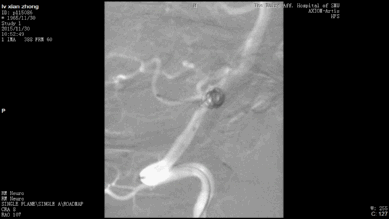

今天为大家分享的是“强生医疗CNV-神经介入专栏”第二十五期,由南方医科大学第三附属医院神经外科主任黄理金教授带来的“Enterprise支架辅助栓塞动脉瘤的优势”精彩讲课视频及PPT,欢迎观看。文章仅代表作者个人观点,如有不同见解,欢迎同道斧正!